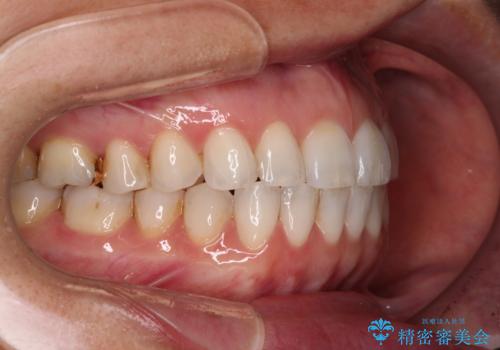

ちょっとしたデコボコをしっかりと改善したい インビザライン矯正

- 前歯のデコボコと上下スペースと前歯の隙間を気にして来院された患者様です。

目立たない装置を希望とのことでインビザラインにより、デコボコを解消しつつ、上下の前歯の隙間を閉じていくこととしました。

デコボコはあっという間に解消されましたが、上下前歯の隙間がなかなか解消されませんでした。

飲み込みの際に舌を前方に突出する癖があり、飲み込みの度に前歯に強く接触していたため、上下前歯の隙間が維持されていました。

舌の訓練を徹底していただいたことで、徐々に隙間は解消され、きれいな歯列に整えることができました。